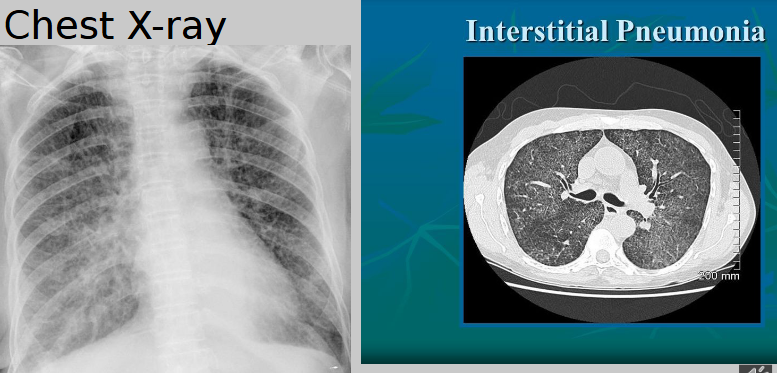

Describe the RA of interstitial pneumonia

mesh-like shadows resulting from linear or reticular opacities — untreated can lead to “honeycomb lung” or cystic spaces as demonstrated by CT